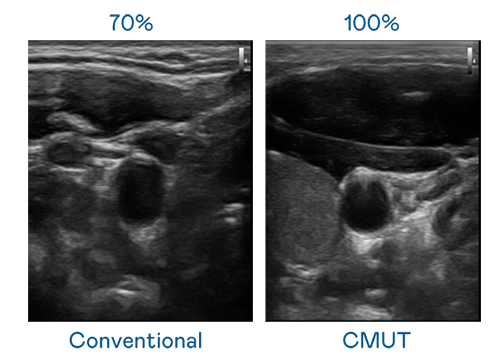

CMUT 技术是一种用电容式微机电元件来产生超音波讯号的技术。与传统 PZT 压电式技术相比,CMUT 频宽增加 30%,更宽频的超音波讯号让影像解析度大幅提升,是实现高影像品质医疗超音波扫描、促进精准医疗发展的关键技术。

超音波影像的解析度高低,首先取决于探头能发出的讯号频宽。ag博天堂 CMUT 可提供高清晰的超音波讯号,提供高频宽、高灵敏度、影像纹理细节更高的超音波影像,协助医护人员缩短影像判读时间及利用精准的医疗影像进行诊断。